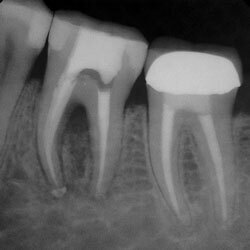

Для пациента такой доктор царь и бог, ведь он кровью и потом "спасал" его несчастную четверочку. Кто ж виноват, что зуб такой. Но правда в том, что терапевт, должен в один момент увидеть, что на этом его полномочия всё и пригласить проконсультироваться коллегу ортопеда, чтобы зуб имел возможность не просто влачить существование, а обрести вторую жизнь под красивым, а главное прочным керамическим колпачком (коронкой).